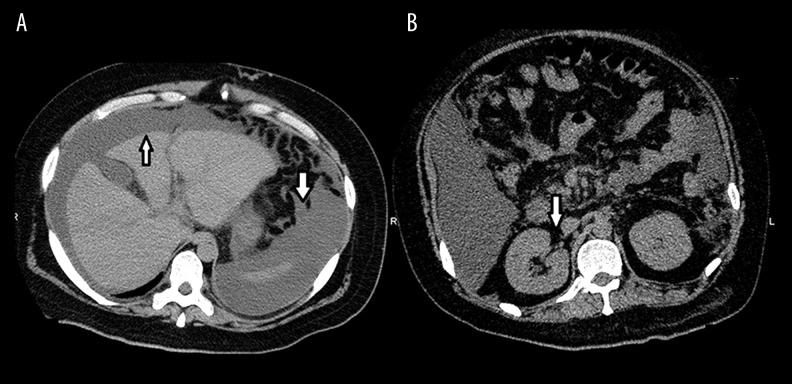

BACKGROUND Hepatorenal syndrome (HRS) is a reversible renal impairment that occurs in patients with acute liver failure and advanced liver cirrhosis. HRS is due to a renal vasoconstriction that results from extreme vasodilatation. It is therefore a functional disorder, not associated with structural kidney damage. On the other hand, end-stage liver diseases are often complicated by massive ascites. Massive ascites may cause abdominal compartment syndrome (ACS), which includes impairment of renal blood flow, but there are no reports indicating that kidney lesions caused by ACS may pathologically contribute to end-stage liver diseases. CASE REPORT A 40-year-old man with acute liver failure was admitted to our hospital. He was diagnosed with type 1 HRS and showed ACS at the same time. He died 30 days after admission. There were signs of congestion in the kidneys upon dissection and advanced erythroid fullness in the renal tubules. CONCLUSIONS We report an autopsy case with HRS and ACS diagnosed with a clinical and histopathological consideration of liver and kidney. Further clinical studies are needed to improve management of renal failure in patients with acute liver failure and advanced liver cirrhosis.

背景 肝肾综合征(HRS)是一种发生于急性肝衰竭和晚期肝硬化患者的可逆性肾功能损害。HRS是由极度血管扩张导致的肾血管收缩引起的。因此,它是一种功能性障碍,与肾脏结构损伤无关。另一方面,终末期肝病常并发大量腹水。大量腹水可能导致腹腔间隔室综合征(ACS),其中包括肾血流受损,但尚无报告表明ACS引起的肾脏病变在病理上会导致终末期肝病。病例报告 一名40岁急性肝衰竭男性入住我院。他被诊断为1型HRS,同时伴有ACS。入院30天后死亡。解剖时肾脏有充血迹象,肾小管有晚期红细胞充盈。结论 我们报告了一例经临床及肝脏和肾脏组织病理学检查确诊为HRS和ACS的尸检病例。需要进一步的临床研究来改善急性肝衰竭和晚期肝硬化患者肾衰竭的管理。